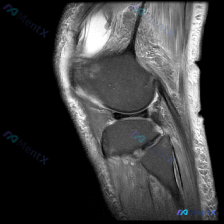

这是一张膝关节矢状位MRI单张图像,临床关注点为「半月板异常」,我们先来看影像的全面评估结果:

- 骨骼结构:股骨远端、胫骨近端、髌骨轮廓完整,无明显骨皮质中断或骨折

- 关节软骨:股骨、胫骨关节面软骨信号均匀,无明显剥脱缺损

- 韧带肌腱:髌韧带、后交叉韧带、股四头肌腱形态信号正常,连续性良好;前交叉韧带全程未在这个切面上显示,属于单一矢状位的正常情况

- 半月板评估:显示的半月板体部及部分角部信号均匀低信号,没有看到异常高信号延伸至关节面,无明确撕裂征象

- 关节与周围软组织:关节间隙正常,无明显异常积液;腘窝、髌下脂肪垫未见异常信号